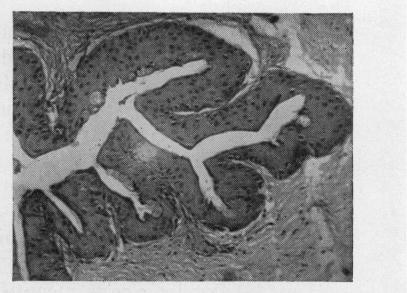

CYST OF DUCT OF KRAUSE'S GLAND.